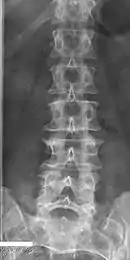

Sacralization of the L5 vertebra is seen at the lower right of the image.

Sacralization of the fifth lumbar vertebra (or sacralization) is a congenital anomaly, in which the transverse process of the last lumbar vertebra (L5) fuses to the sacrum on one side or both, or to ilium, or both. These anomalies are observed in about 3.5 percent of people, and it is usually bilateral but can be unilateral or incomplete (ipsilateral or contralateral rudimentary facets) as well. Although sacralization may be a cause of low back pain, it is asymptomatic in many cases (especially bilateral type). Low back pain in these cases most likely occurs due to biomechanics. In sacralization, the L5-S1 intervertebral disc may be thin and narrow. This abnormality is found by X-ray.